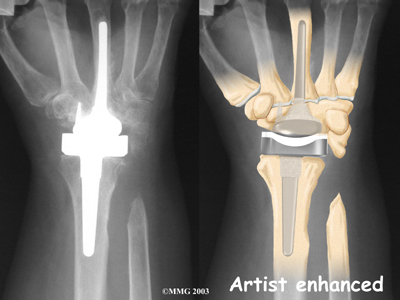

The wrist joint is replaced with an artificial joint (also called a prosthesis) much less often than other joints in the body, such as the knee or the hip. Still, when necessary, this operation can effectively relieve the pain caused by wrist arthritis. When severe arthritis has destroyed the wrist joint, artificial wrist replacement surgery (also called wrist arthroplasty) can help restore wrist strength and motion for many patients.

The wrist is made up of eight separate small bones, called the . The carpal bones connect the two bones of the forearm, the radius and the ulna, to the bones of the hand. The metacarpal bones are the long bones that lie mostly underneath the palm. The metacarpals are in turn attached to the phalanges (the bones in the fingers and thumb).

One reason that the wrist is so complex is that every small bone forms a joint with the bone next to it. This means many small joints make up the wrist joint. Ligaments connect all the small bones to each other, and to the radius, ulna, and metacarpal bones.